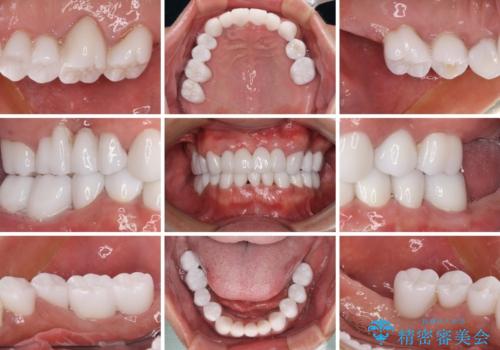

欠損と虫歯だらけの口の中 真っ白なセラミック治療

インプラントにより奥歯の咬み合わせが安定し、上顎前歯の歯肉ラインを調整するための骨外科処置により深く咬みこんでいた前歯部も負担のかからない咬み合わせに改善することができました。

治療終了直前に転勤となってしまい、最後2回の来院は新幹線にて来院いただくことになってしまいましたが、短期間で無事に終了することができました。